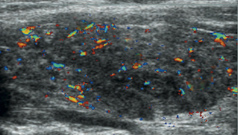

Graves disease

A

Hyperthyroidism (‘toxic goiter’)

• *Autoimmune disease:** immune system attacks thyroid → excess production TH → thyrotoxicosis

• Women >30

• Diagnosis

• Clinical/ lab: low TSH, high T3/T4

• US useful if asymetric enlargement

• Treatment

• TSH receptor blocker (medical)

• Thyroidectomy

Uniformly enlarged thyroid

Hypoechoic

Heterogeneous echotexture

Hypervascular (‘Thyroid inferno’)

Differential = Hashimoto’s Thyroiditis